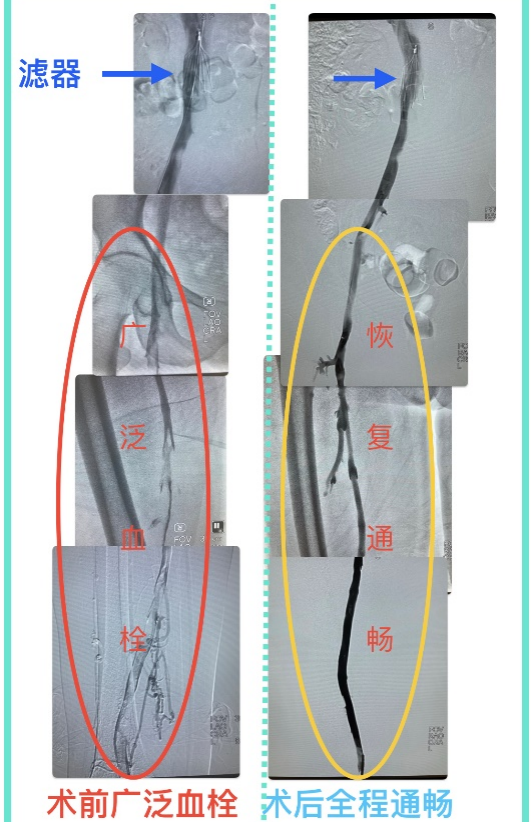

手术前后深静脉血栓变化情况:术前深静脉内广泛血栓,术后血栓清除满意,血流恢复通畅